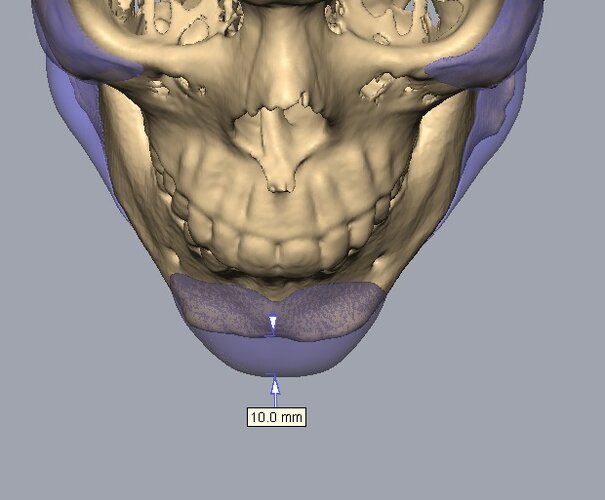

Recieved the draft 1 of the design, what changes should i ask for?? a couple of things i can think of are malar implants not giving enough lateral protrusion, gonion flaring.

I also am planning to include infra implants as well.